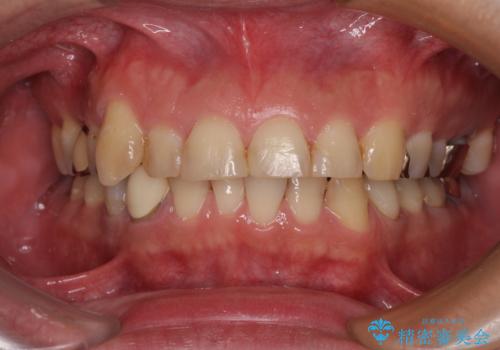

気になっていたむし歯と前歯のデコボコ 矯正治療とむし歯治療の総合歯科治療